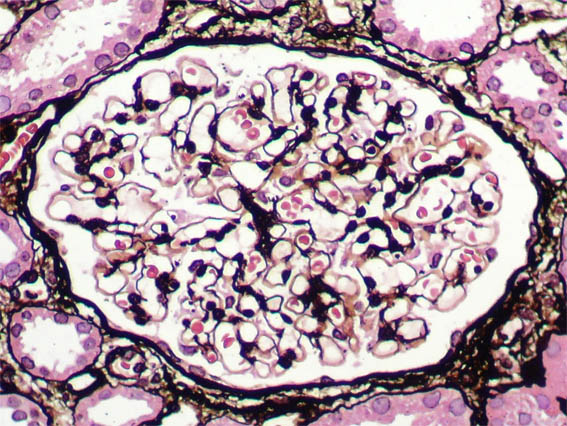

Figura 6.

Tricrómico de Masson, X400.

Figura 7.

Plata-metenamina, 400.